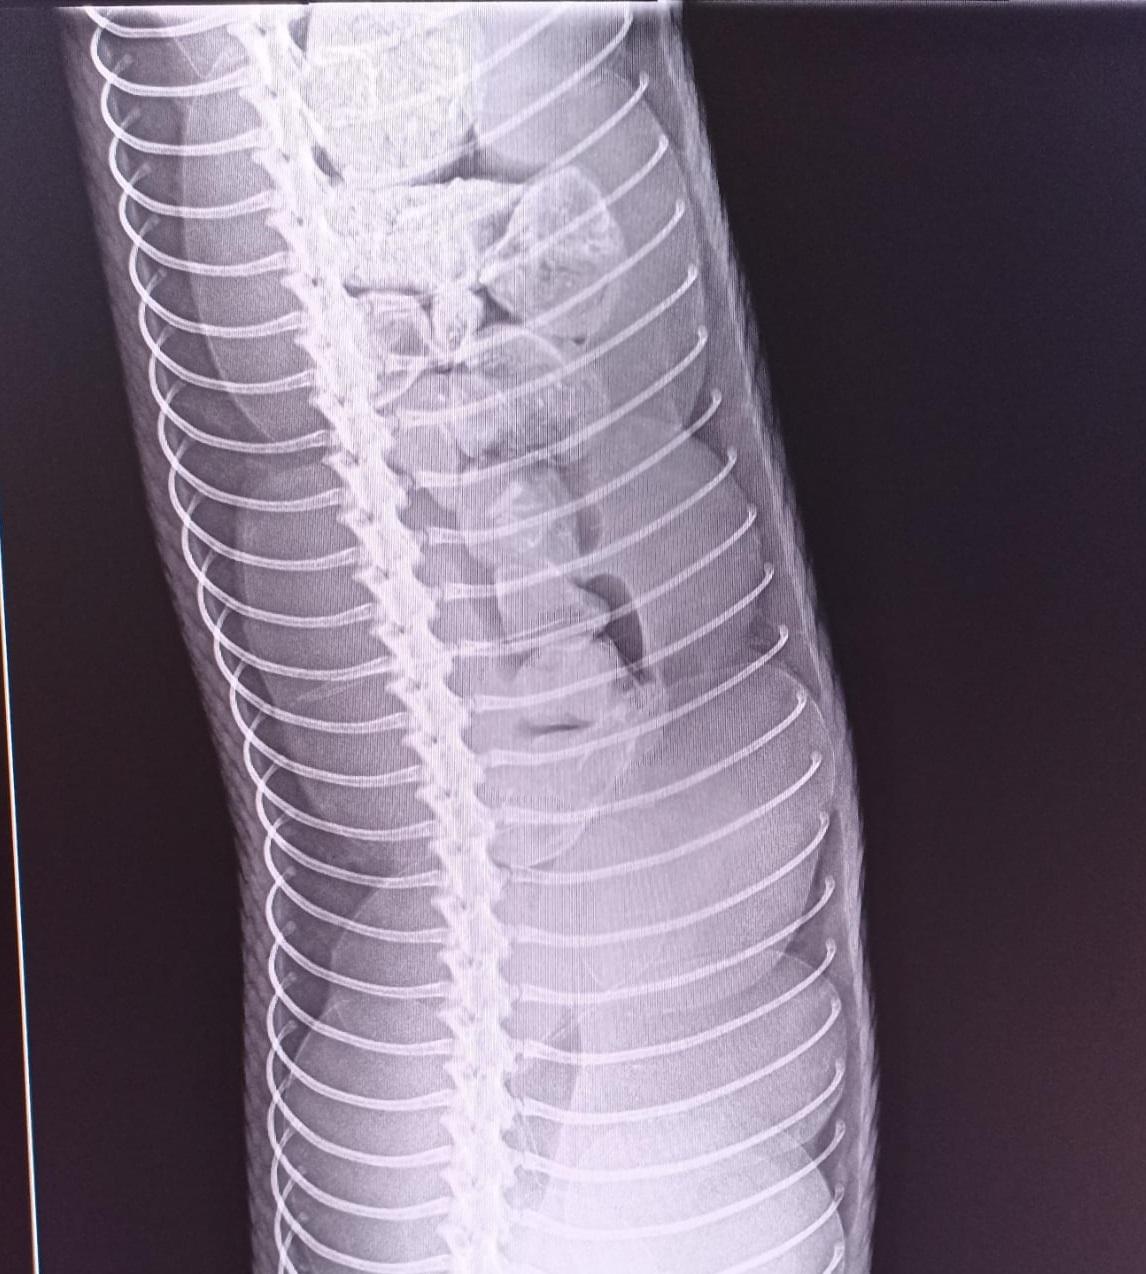

Bár a rendelőben rendszeresen látnak el kígyókat, Gizi esete mérete miatt is különleges volt. A tapintásos vizsgálat már sejtette a problémát, de végül egy röntgenfelvétel erősítette meg a gyanút. Az állatorvosok nem késlekedtek: műtéti altatásban megnyitották a kígyó testüregét és a tojócsövét, majd összesen 38 tojást távolítottak el – több órás, két szakember által végzett műtét során.

A műtét során kiderült, hogy a tojócső vége már begyulladt, néhány tojás pedig bomlani kezdett – ez tette még sürgetőbbé a beavatkozást. A műtét után Gizit fájdalomcsillapítóval, gyulladáscsökkentővel és antibiotikummal látták el, majd hat héttel később eltávolították a varratokat is. A jó hír: Gizi azóta jól van, és vidáman tekergőzik tovább.